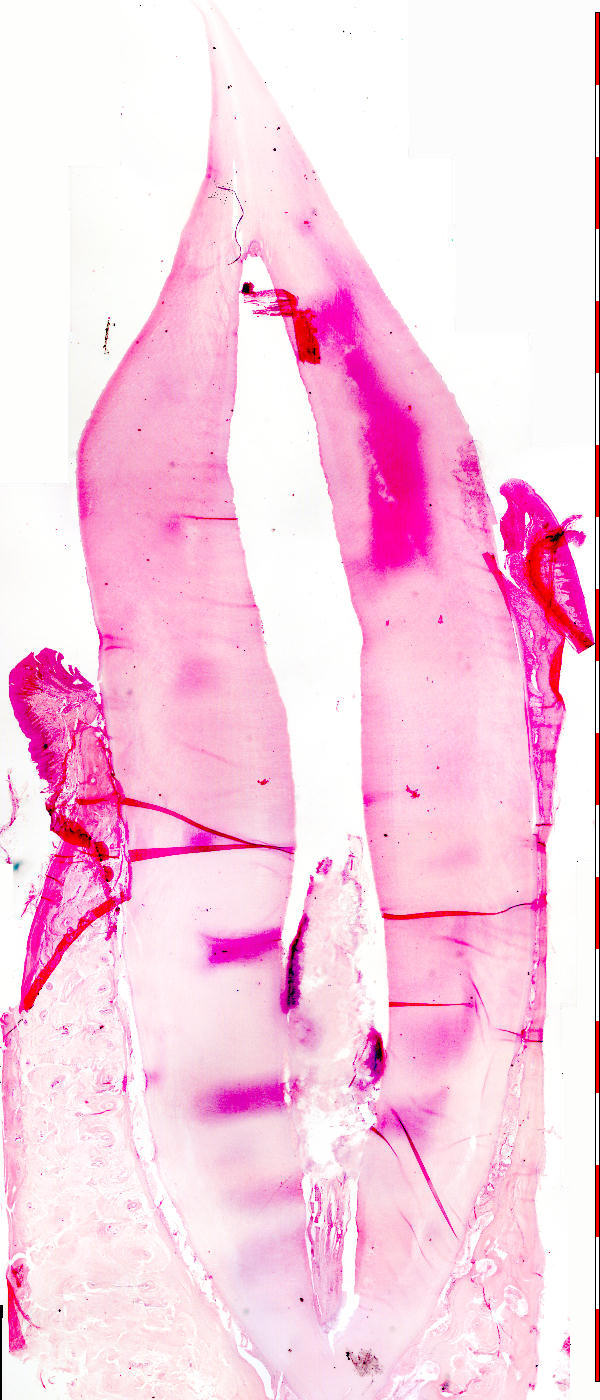

Tandsnit (lengtesnit)

Tooth (longitudinal section)

© augustus 2007 marius loots